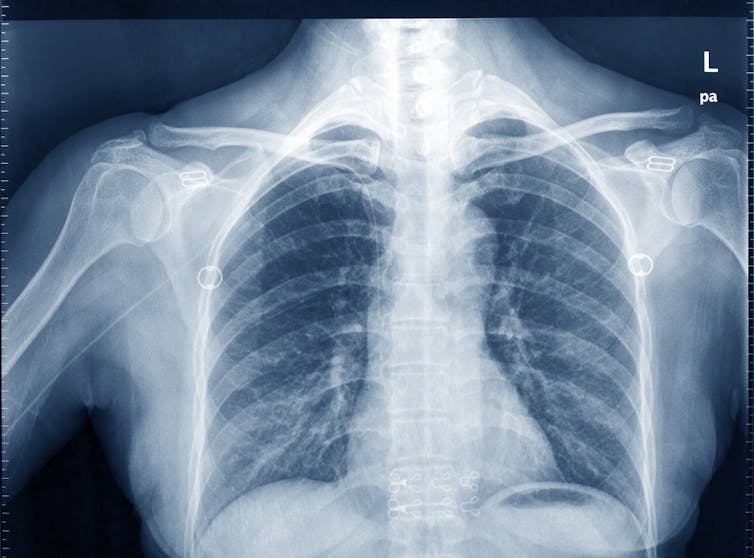

‘X-rays’ or planar radiography

This is still the most common, widely-available and simplest form of medical imaging, often used to see a broken bone. X-rays are actually photons, or tiny packets of energy (referred to as ionizing radiation) and form part of the electromagnetic spectrum (as does visible light, microwaves and radio waves).

As an x-ray beam passes through human tissue, these x-ray photons can be absorbed and deflected by dense tissue structures such as bone and may not exit the body. Other x-ray photons may encounter tissue that is less dense (such as muscle) and are able to pass through this quite easily and exit the body.

The exiting x-ray photons then reach a digital imaging receptor or detector where they provide a tissue density pattern for the digital receptor to convert into the x-ray image (or radiograph) that we are familiar with.

Dense tissue such as bone that has attenuated the x-ray beam appears dense or white; less dense tissue such as lungs that are filled with air appear less dense or dark, which we observe with a “chest x-ray”. Other tissues in the human body have densities between these two extremes and appear on an x-ray image as different shades of grey.

Patients should be reassured this form medical imaging is straight-forward, and there should be no risk or danger from the radiation when used correctly.